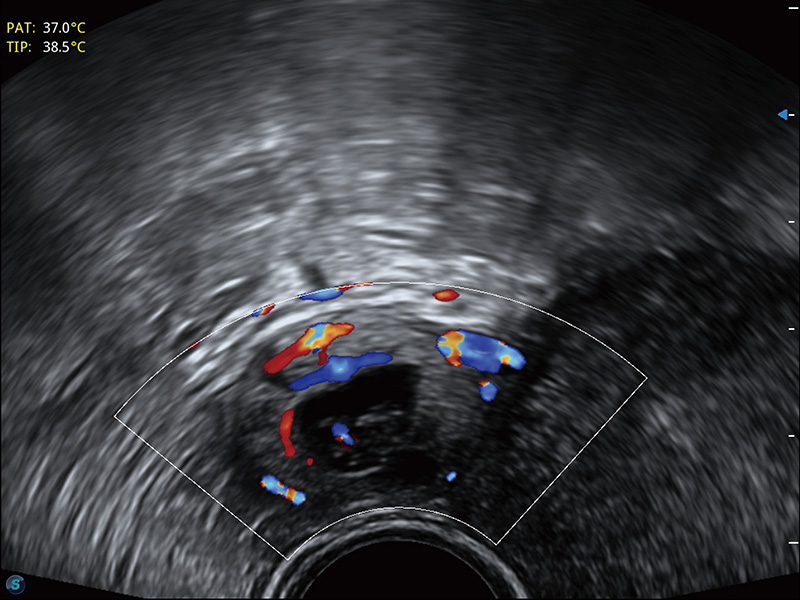

“生育问题”即关系民族复兴,也关系亿万家庭的幸福。随着婚育年龄推迟、社会压力增加等因素,越来越多人群也面临着“生不出、生不好”的问题。辅助生殖作为治疗不孕不育最有效的方法之一,也逐渐成为育儿新希望。而超声检查能为生殖需求人群的初诊评估提供宝贵的信息。 P20 Elite是开立医疗匠心打造的一款生殖应用型彩超。她继承开立医疗高端极光平台,突破性地将多款新型芯片及硬件模块进行整合,均衡了高端系统性能与小巧灵动机身。P20 Elite卓越的图像质量搭载专科探头,旨在为您提供全面的辅助生殖解决方案。

P20 Elite配备了丰富的生殖探头群和临床应用功能,在卵泡监测、穿刺取卵、胚胎移植、妊娠确认等领域,为生殖需求人群提供了新的临床机会,重新定义高端超声如何应用于生殖健康检查。

耦合剂加热器可将耦合剂维持在舒适的温度,体现患者关爱。